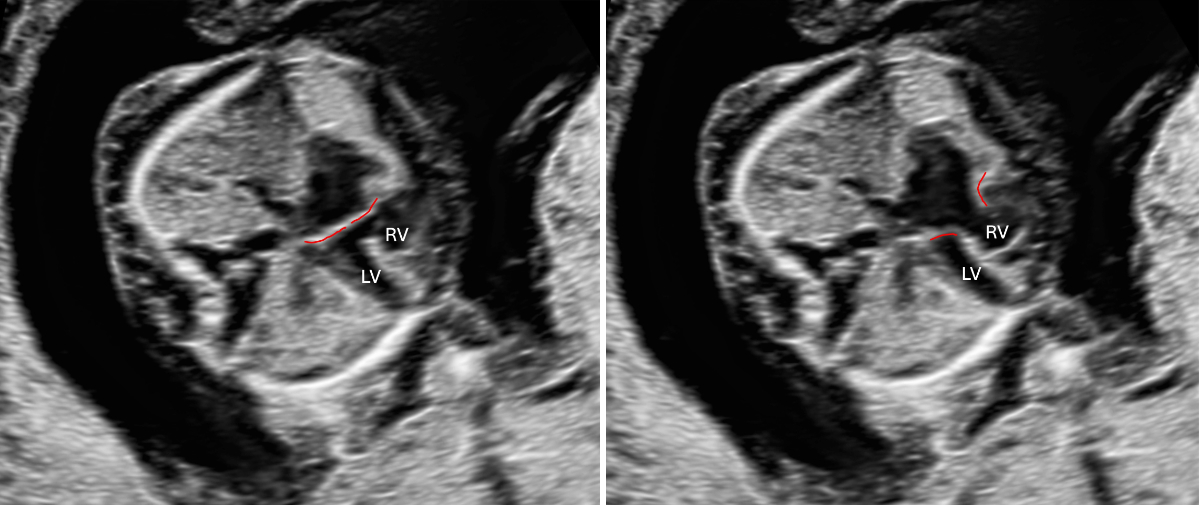

First trimester screening is not limited to detecting trisomies 13/18/21; it is essential for early identification or exclusion of many major structural anomalies (see figures 3–5). According to the current Swiss guidelines [3], combined testing for trisomies should be offered only when no significant malformations have been found and when nuchal translucency is below the 95th centile. Otherwise, diagnostic procedures should be offered.

Figure 3Atrioventricular septal defect in a 13-week foetus with trisomy 21, atrioventricular valve highlighted in red. Left: AV valve closed (systole); right: AV valve open (diastole). LV: left ventricle; RV: right ventricle.